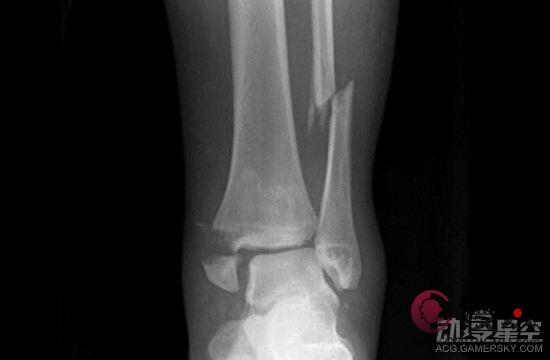

有网友在推特上发文称看到同事用这种方法锻炼,结果很惨烈:“同事在两个月内做了《一拳超人》中的训练,从78公斤减到65公斤,不幸的是他踝关节骨折需要休息8周。这种锻炼每天都得做,对身体的负担很大,我想说你得了解自己的身体状况而不是直接照做啊。”